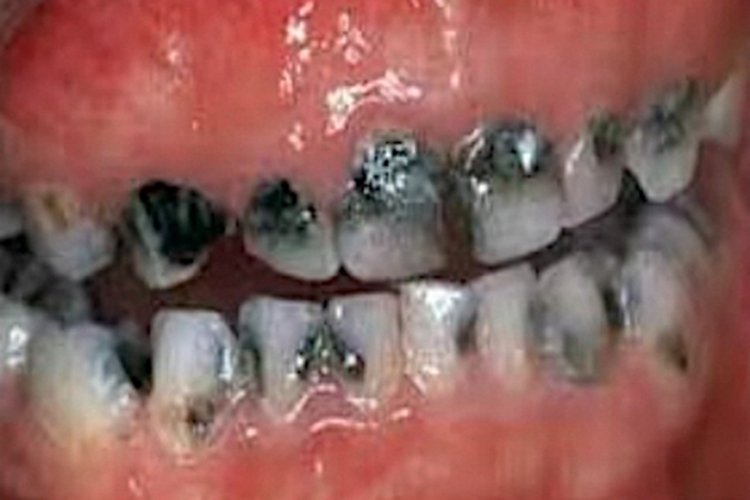

低龄儿童龋黑斑图

猖獗龋黑斑图